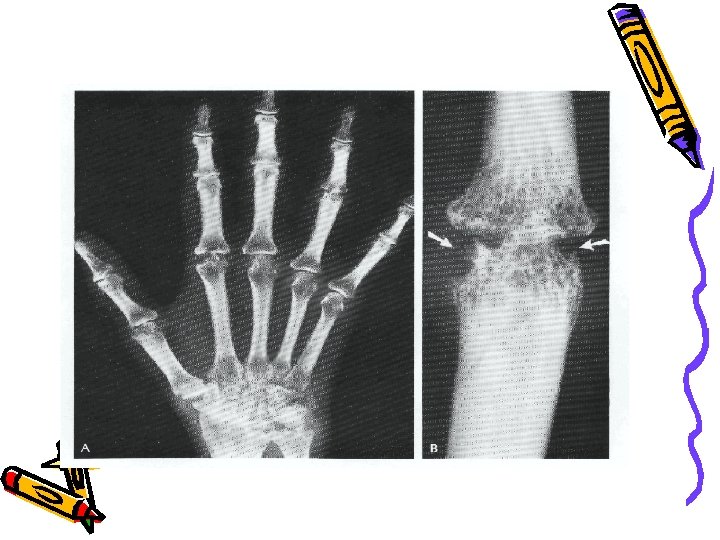

Рентгенологічні ознаки: • 11. Остеопороз, дрібнокістозна перебудова кісткової структури епіфіза. • 12. Звуження суглобових щілин, кісткові ерозії, анкілоз суглобу. • 13. Порушення росту кісток. • 14. Ураження шийного відділу хребта. • Лабораторні ознаки: • 15. Позитивний РФ. • 16. Позитивні дані біопсії синовіальної оболонки. • * 3 ознаки - ймовірний ЮРА; • 4 ознаки - визначений ЮРА; • 8 ознак - класичний ЮРА при обов‘язковій наявності першої ознаки.

Диференціальний діагноз суглобової форми РА та Ре. А Симптом ЮІА Рентгенограма суглобів На початку – остеопороз, зміни суглобової щілини, на пізніх етапах - анкілози М. б. розширення суглобової щілини при великому ступені ексудації УЗД суглобів Випіт в порожнину суглоба, гіпертрофія або проліферація синовіальної оболонки, ураження суглобового хряща, кісткові ерозії Випіт в порожнину суглоба, тривалому перебігу – незначна гіпертрофія синовіальної оболонки Відповідь на НПЗЗ Лише у початковій фазі Добра, швидка Лейкоцитоз При загостреннях Виражений РФ Позитивний до 10 % Негативний Анти - ЦЦП М. б. позитивний Завжди негативний